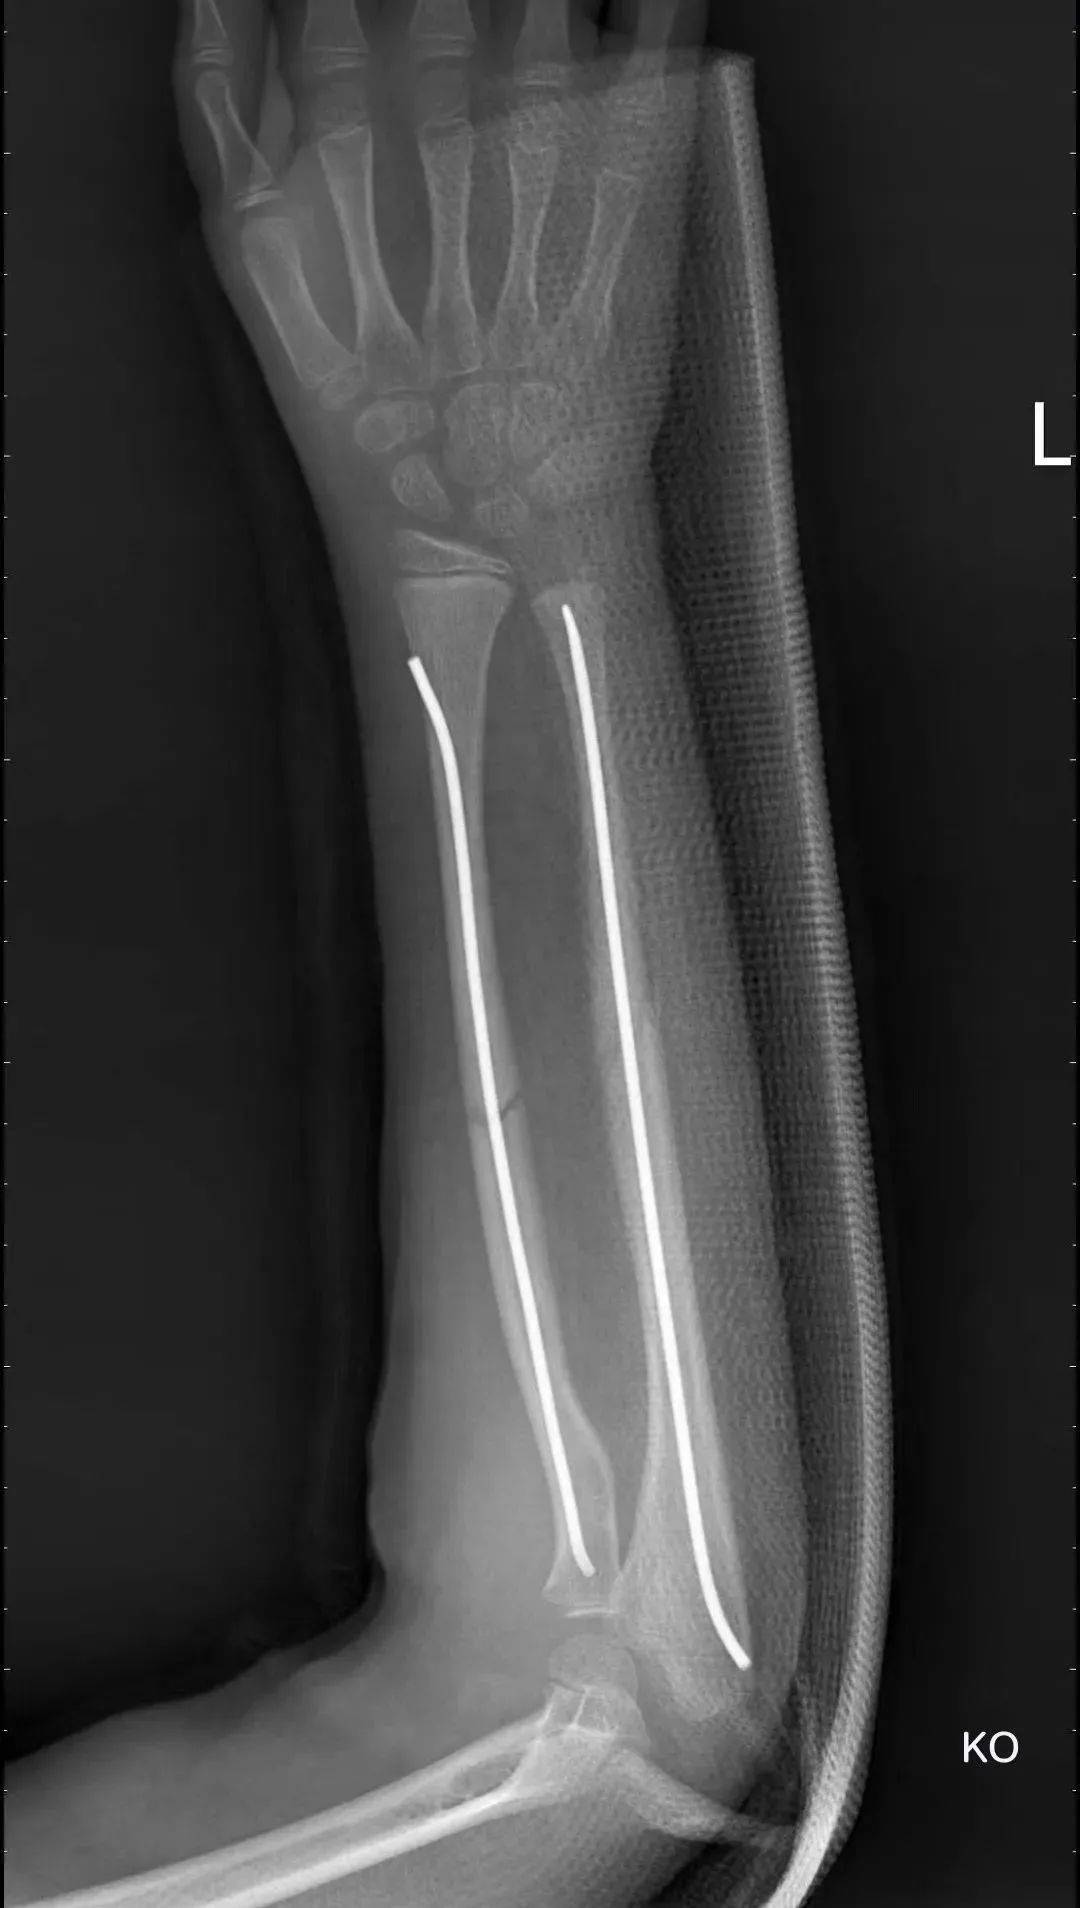

我们采取微创弹性钉内固定治疗,手术切口仅需2厘米,保证复位固定的同时满足了减少瘢痕的需要。

弹性钉固定后骨折复位满意

切口仅仅2厘米,微创,术后瘢痕少,骨折愈合快。

术后第2天患儿就蹦蹦跳跳的下床玩耍,跟之前的保守治疗状态天壤之别,患儿的奶奶也非常高兴,孩子不疼了,也有精神头玩耍了,仅仅住院4天就出院回家了。